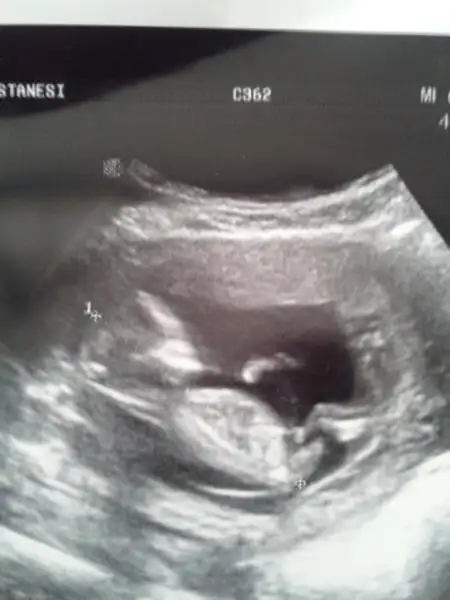

dr soylemeden siz gorun genital nub teorisi ( bebegin cinsiyeti)

Iki kizimdan sonra birde oglum olacakmis allahin izniyle..